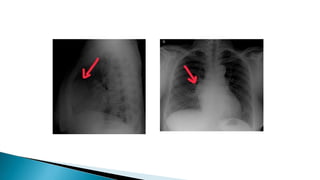

• Chest CECT scan is the imaging procedure of

choice in patients with MG.

– Thymic enlargement should be determined because

most enlarged thymus glands on CT scan represent

a thymoma.

– CT scan with intravenous contrast dye is preferred

– to show the relationship between the thymoma and

surrounding vascular structures,

– to define the degree of its vascularity, and

– to guide the surgeon in removal of a large tumor,

possibly involving other mediastinal structures

• Chest CECTscan is the imaging procedure of choice in patients with MG. – Thymic enlargement should be determined because most enlarged thymus glands on CT scan represent a thymoma. – CT scan with intravenous contrast dye is preferred – to show the relationship between the thymoma and surrounding vascular structures, – to define the degree of its vascularity, and – to guide the surgeon in removal of a large tumor, possibly involving other mediastinal structures